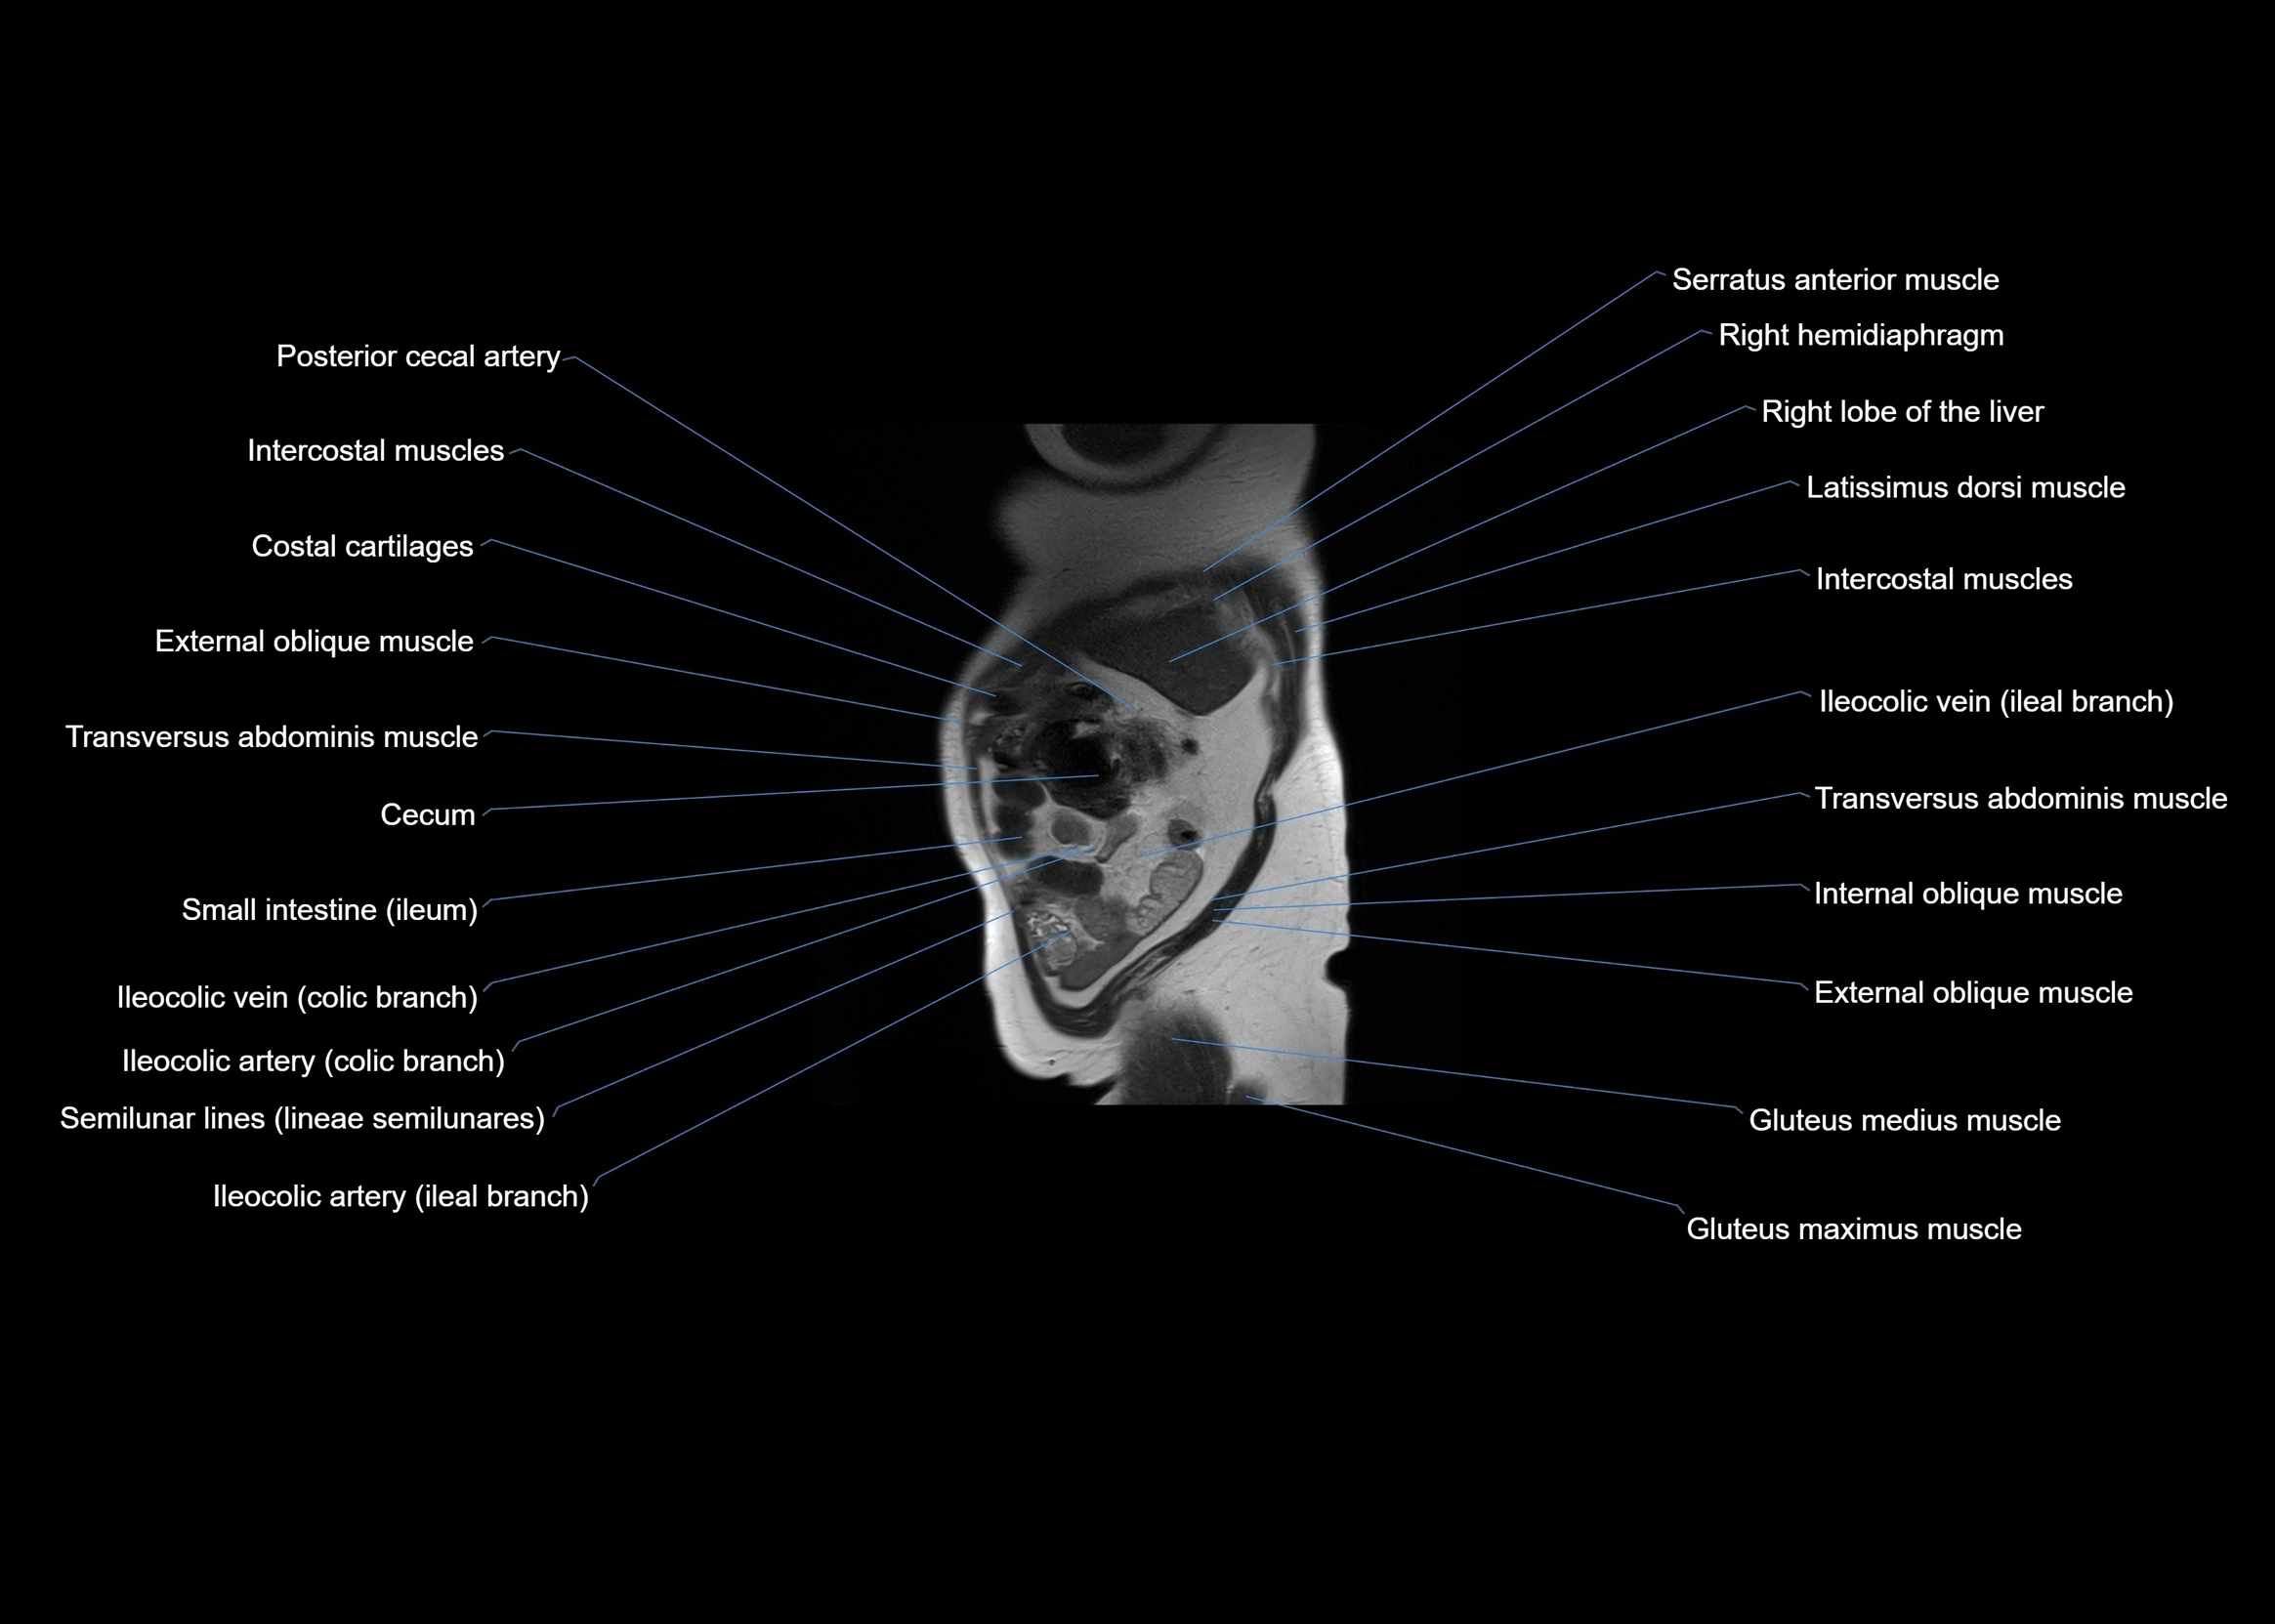

MRI images